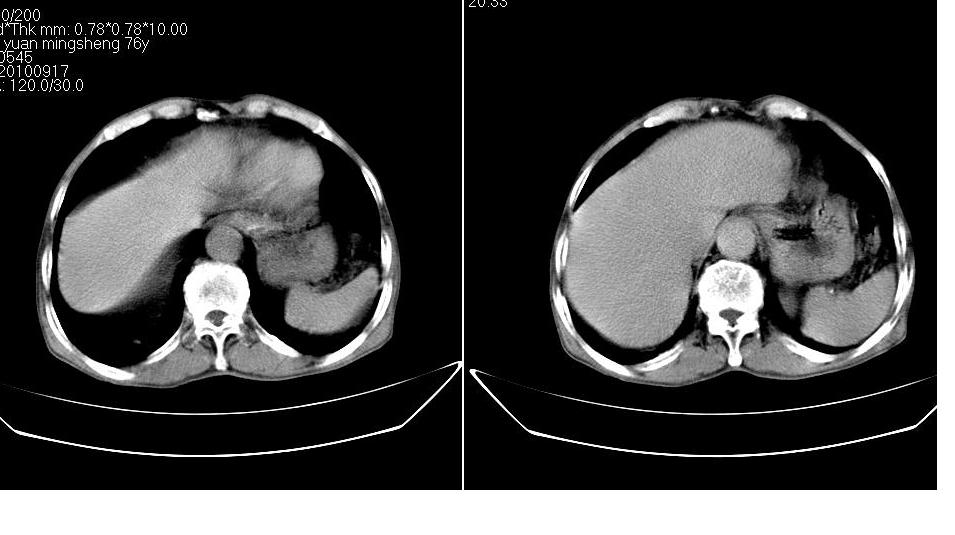

男,76岁,上腹部疼二天来就诊,彩超提示肝左叶占位,随后做上腹部ct平扫,今天做上腹部ct增强扫描,手工推药,效果不好,请谅解。

肝左叶s4肿块强化形式大概是:慢进慢出,逐渐强化----考虑血管瘤/腺瘤?{动脉期应更提前扫}。

肝右叶前段hcc

1)肝右叶前段低密度灶,不排除肝癌可能;建议查afp。2)右肾上极囊肿。

肝内胆管积气扩张,胆囊增大,肝右前叶低密度灶,逐渐强化,一元论,胆系感染,局限性肝脓肿;右肾囊肿。

考虑肝s4段肝脓肿可能?未排除肝癌。右肾上极囊肿。